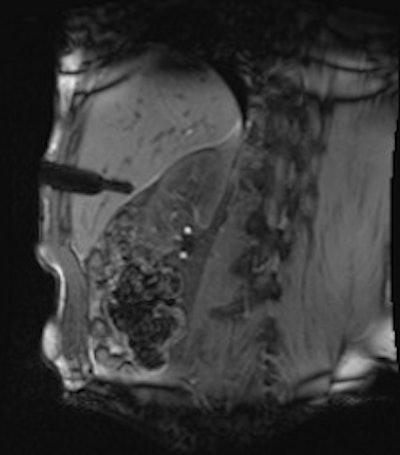

A 50-year-old man with history of pancreatic carcinoma underwent a CT-guided biopsy (above), which was nonconclusive (pathology result: normal liver tissue). Three weeks later, an MR-guided biopsy (below) was performed, and the biopsy revealed a cavernous hemangioma. Images courtesy of Dr. Rüdiger Hoffmann.